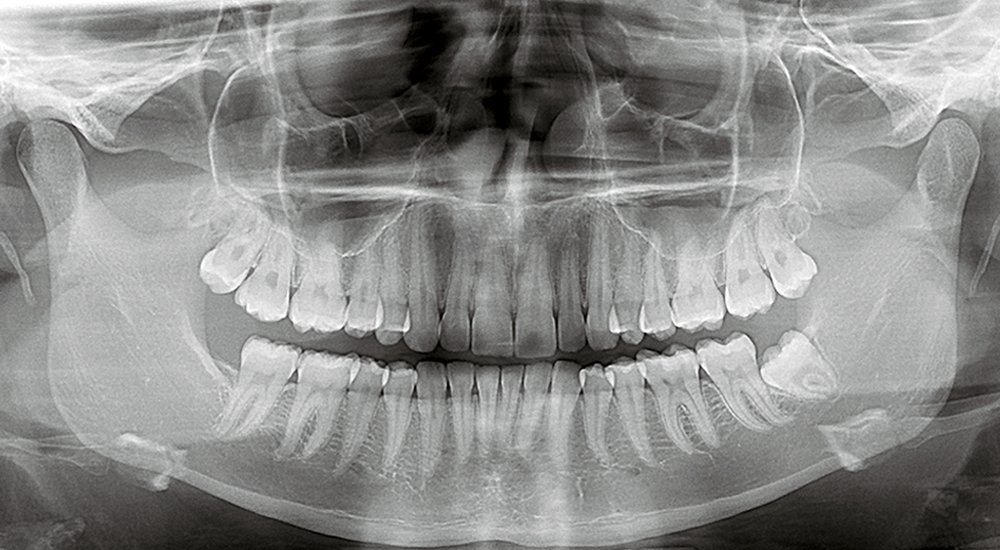

Examens radiographiques

Une radiographie panoramique complétée par des radiographies rétro-alvéolaires et rétro-coronaires est indispensable pour :

- Un bilan général de l’état bucco-dentaire

- La détection de foyers infectieux et pathologies osseuses, évaluation de poches parodontales

- La détection des processus carieux